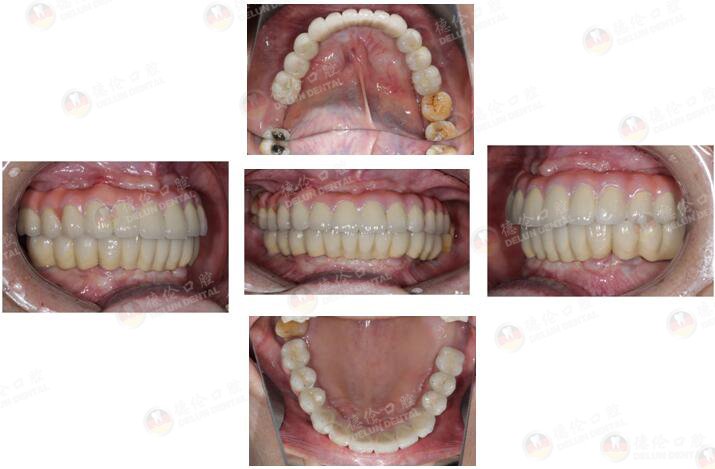

治疗方式:倾斜植体避开左侧上颌窦、整体支架修复、数字化3D导板种植